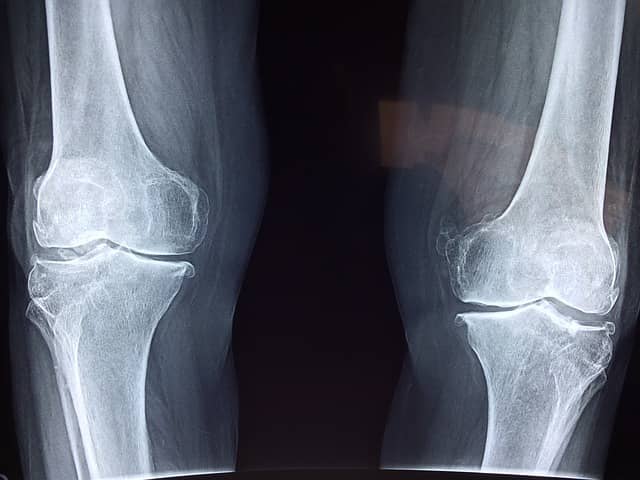

이는 골밀도가 감소하고 뼈의 구조가 파괴되면서 발생하는데요, 이에 따라 뼈는 여러 구멍이 나 마치 꿀단지처럼 보일 수 있어 '골다공증'이라는 이름이 붙었답니다.

먼저 척추에 골다공증이 발생하면 허리통증이 나타날 수 있습니다. 처음에는 가벼운 통증으로 시작하지만, 질병이 진행될수록 통증이 점점 심해질 수 있습니다. 또 골다공증 증상으로 뼈가 약해지면, 간단한 충격이나 낙상만으로도 골절이 일어날 수 있습니다. 특히 손목이나 허리뼈, 엉덩이, 골반의 골절이 일어나기 쉽습니다.